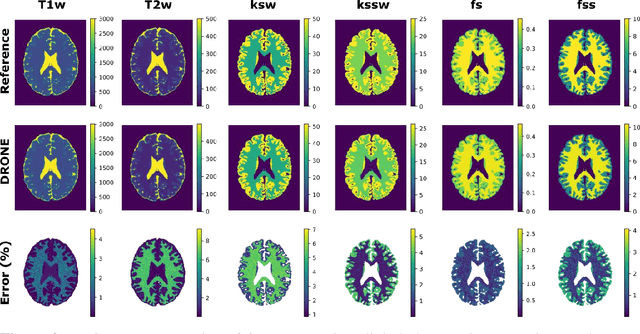

Purpose: To develop a clinical chemical exchange saturation transfer magnetic resonance fingerprinting (CEST-MRF) pulse sequence and reconstruction method. Methods: The CEST-MRF pulse sequence was modified to conform to hardware limits on clinical scanners while keeping scan time $\leqslant$ 2 minutes. The measured data was reconstructed using a deep reconstruction network (DRONE) to yield the water relaxation and chemical exchange parameters. The feasibility of the 6 parameter DRONE reconstruction was tested in simulations in a digital brain phantom. A healthy subject was scanned with the CEST-MRF sequence and a conventional MRF sequence for comparison. The reproducibility was assessed via test-retest experiments and the concordance correlation coefficient (CCC) calculated for white matter (WM) and grey matter (GM). The clinical utility of CEST-MRF was demonstrated in a brain metastasis patient in comparison to standard clinical imaging sequences. The tumor was segmented into edema, solid core and necrotic core regions and the CEST-MRF values compared to the contra-lateral side. Results: The 6 parameter DRONE reconstruction of the digital phantom yielded a mean absolute error of $\leqslant$ 6% for all parameters. The CEST-MRF parameters were in good agreement with those from a conventional MRF sequence and previous studies in the literature. The mean CCC for all 6 parameters was 0.79$\pm$0.02 in WM and 0.63$\pm$0.03 in GM. The CEST-MRF values in nearly all tumor regions were significantly different (p=0.001) from each other and the contra-lateral side. Conclusion: The clinical CEST-MRF sequence provides a method for fast simultaneous quantification of multiple tissue parameters in pathologies.